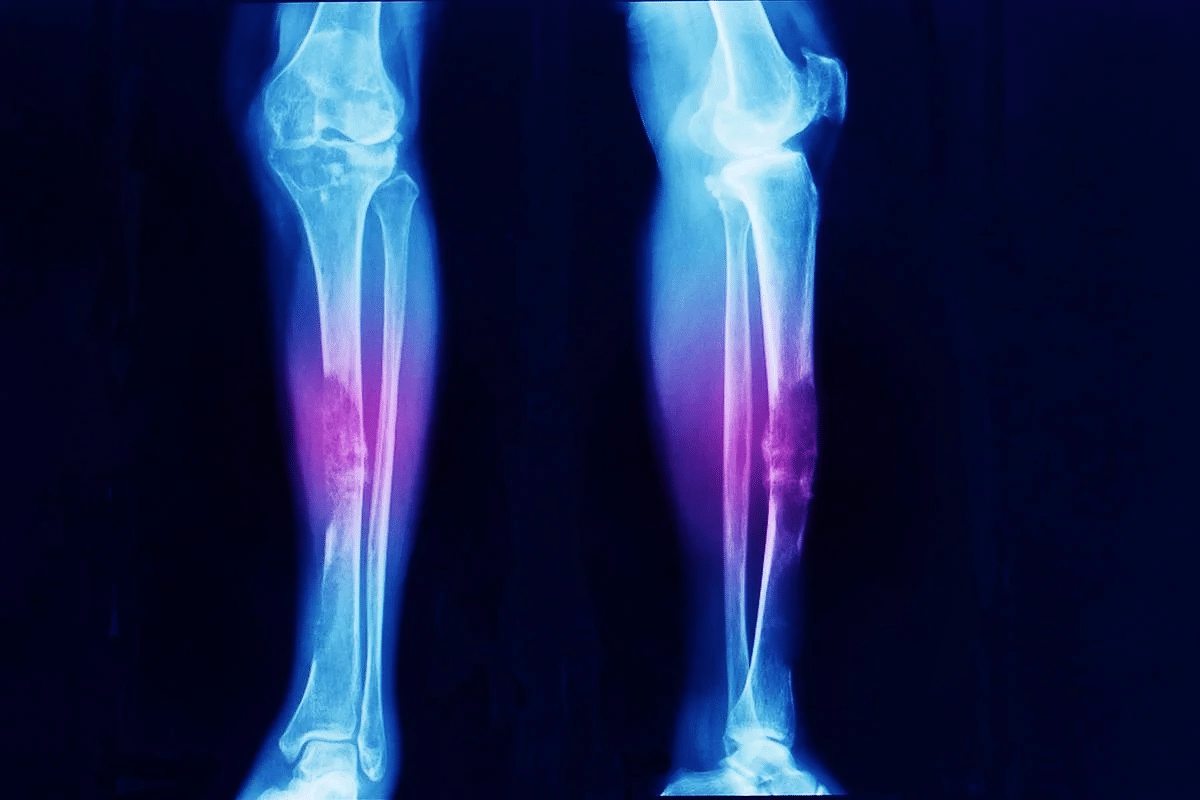

Bone cancer in the legs can occur in different parts. This includes the femur (thigh bone), tibia and fibula (lower leg bones), and the bones of the knee and ankle. The femur is a common site for osteosarcoma.

The location of the cancer in the leg affects symptoms and treatment. Accurate diagnosis and staging are vital for a good treatment plan.